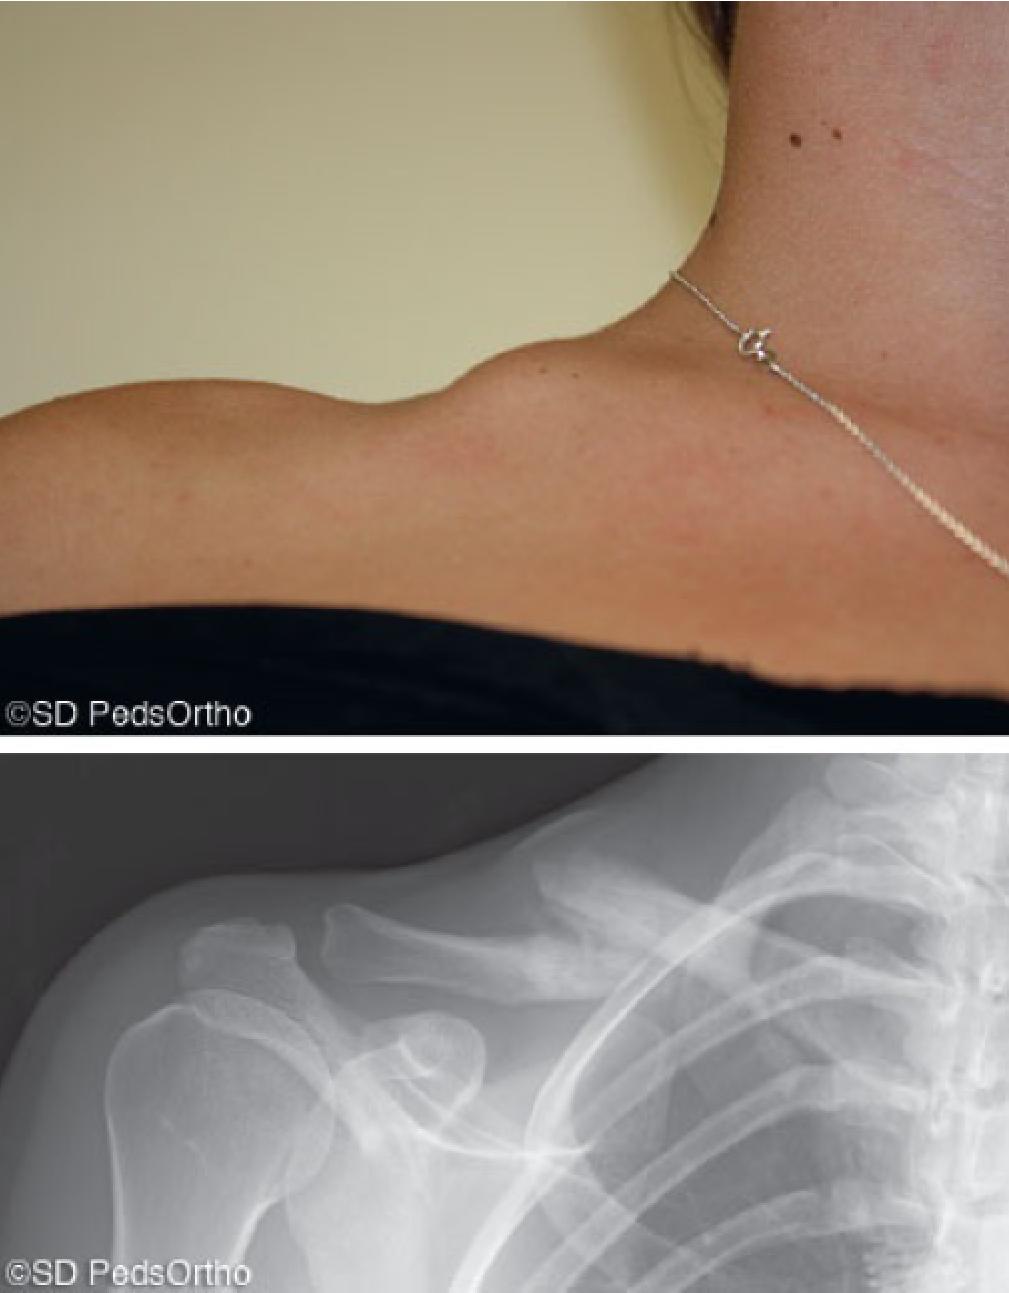

骨折端向上凸起,可能刺穿皮肤变为开放性骨折

悬吊固定

锁骨骨折吃什么食物最好,锁骨骨折怎么绑绷带视频

“8”字绷带固定